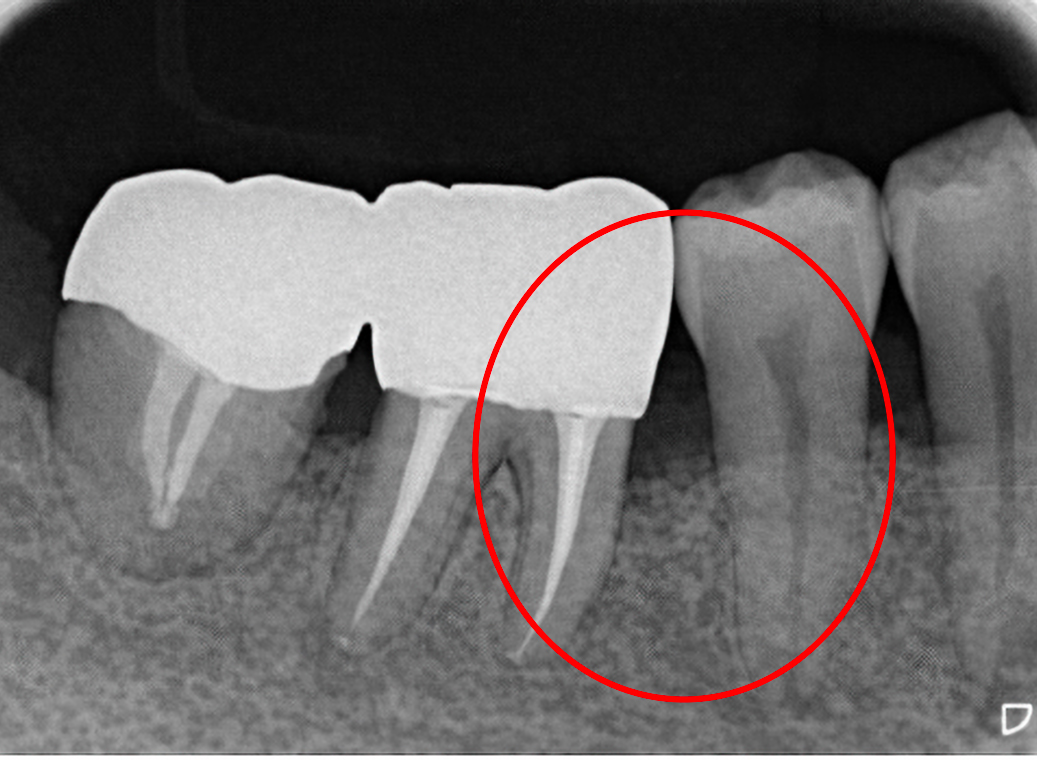

奥歯のグラグラ。通常は抜歯検討となる『根分岐部病変』(奥歯の歯根が分岐した部分:根分岐部に細菌感染が起こり、歯の周りの骨が吸収してなくなる病気)を骨再生療法により、保存しました。経年後も維持しています。

治療前

治療後 4年後

奥歯の骨吸収(歯の周りの骨が吸収してなくなる病気)で動揺している歯を骨再生療法により保存しました。また、歯ぐきに埋まっている親知らずの埋伏抜歯をしました。経年後も維持しています。

治療後 5年後